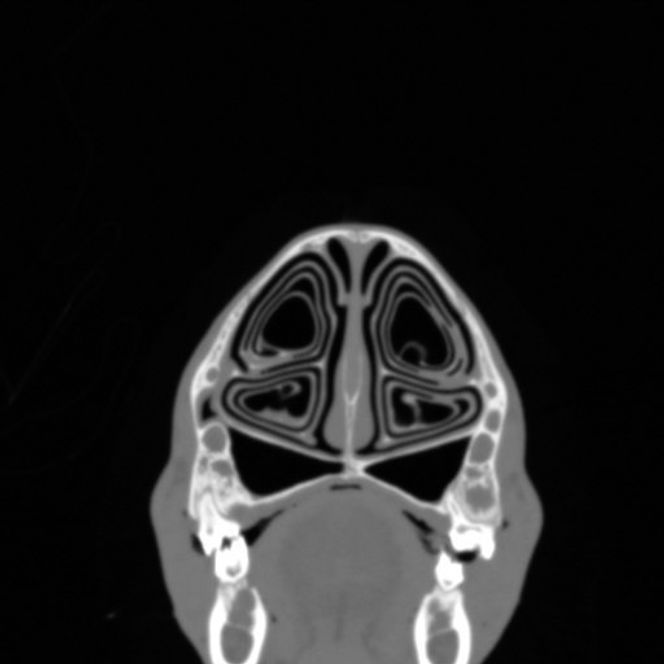

En reinsdyrnese har da blitt delt opp i skiver og CT-skannet. Slik har forskerne skaffet seg tverrsnittbilder av pusteorganet i hele sin lengde. Bildene viser at nesen innvendig har en uvanlig og underlig struktur. Den ligner på en konkylie.

Også den indre overflate ble målt, og viste seg å være enorm. På hvilken måte? Tenk på norskekysten. Måler vi den faktiske lengden på kysten, inkludert alle kroker og kriker, ser vi at kysten vår er enormt lang. Slik er det med reinsdyrnesens indre overflate også. En stor indre overflate betyr at det er mye plass for å utveksle varme og vanndamp mellom luften og neseveggen.